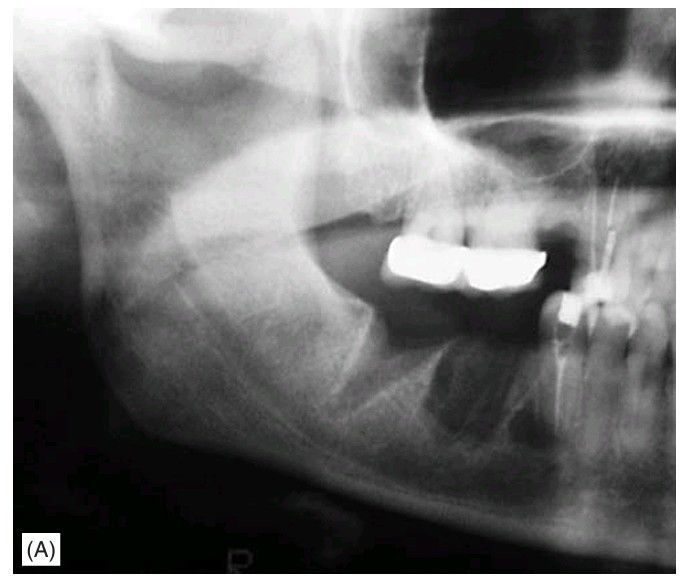

Bisphosphonate-induced osteonecrosis.

Non-healing extraction sockets in a breast cancer patient receiving bisphosphonate treatment.